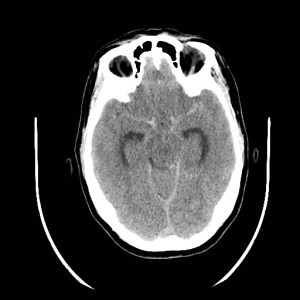

Grado 1- No se detecta sangre en la TAC craneal.